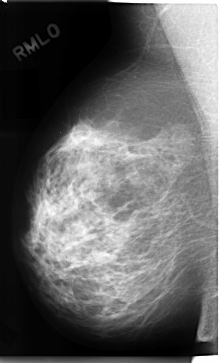

C_0080_1.RIGHT_MLO

RIGHT_MLO LINES 4712 PIXELS_PER_LINE 2848 BITS_PER_PIXEL 12 RESOLUTION 50 NON_OVERLAY